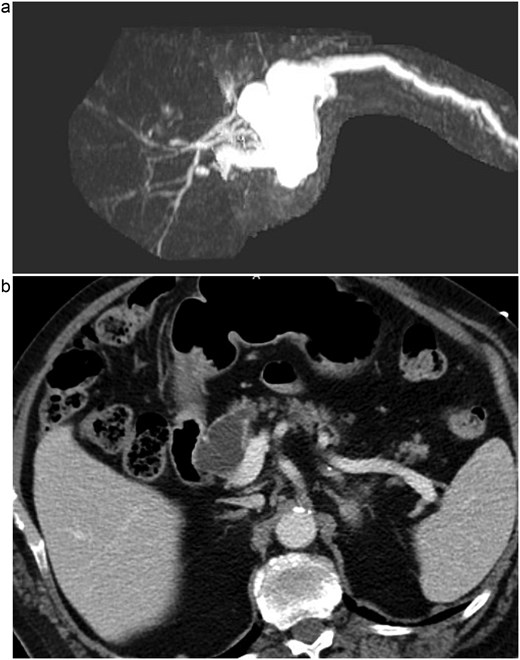

A 76-year-old male presented initially to the emergency department with concerns of chest pain. His medical history included mild dementia, CHF, aortic stenosis, hypertension, hyperlipidemia, CKD, GERD, and chronic constipation without prior abdominal surgeries. His cardiac workup was negative, however, a CT of his abdomen demonstrated concerns for pancreatic duct dilation. Additionally, MRI evaluation demonstrated a cystic mass at the head of the pancreas that communicated with the main pancreatic duct (see Fig. 1). Initial laboratory values included lipase of 711, CEA of 13, CA19-9 of 11, and normal liver function tests without hyperbilirubinemia.

(a) MRI/MRCP imaging of the cystic lesion of the pancreatic head with involvement of the main pancreatic duct. (b) CT imaging illustrating the main duct IPMN at the head of the pancreas.